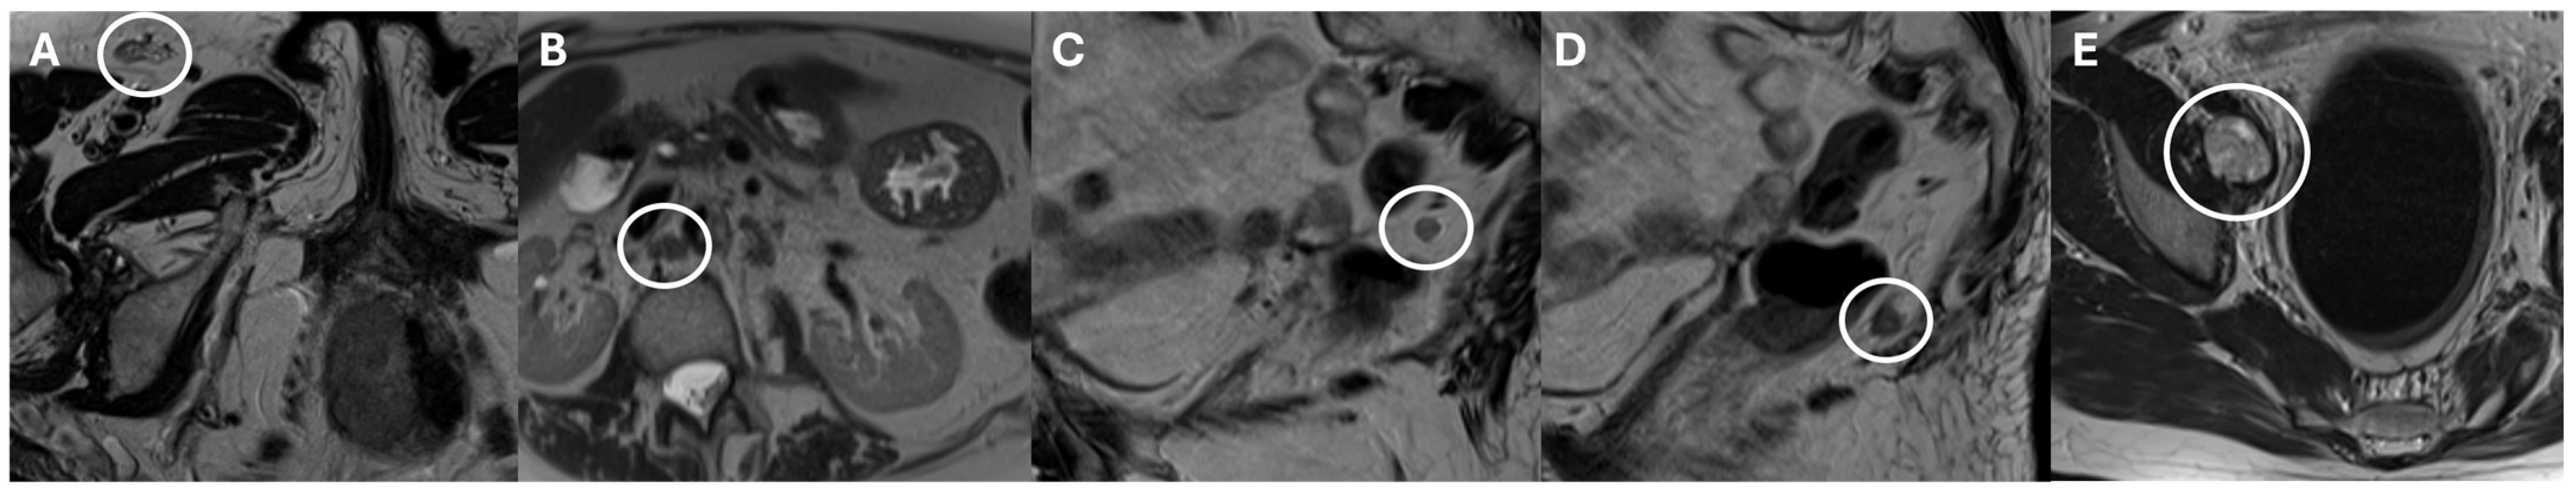

- Ninkova, R.V.; Calabrese, A.; Curti, F.; Riccardi, S.; Gennarini, M.; Miceli, V.; Cupertino, A.; Di Donato, V.; Pernazza, A.; Rizzo, S.M.; et al. The Performance of the Node Reporting and Data System 1.0 (Node-RADS) and DWI-MRI in Staging Patients with Cervical Carcinoma According to the New FIGO Classification (2018). Radiol. Med. 2024, 129, 1062–1075. [Google Scholar] [CrossRef] [PubMed]

- Wu, Q.; Lou, J.; Liu, J.; Dong, L.; Wu, Q.; Wu, Y.; Yu, X.; Wang, M. Performance of Node Reporting and Data System (Node-RADS): A Preliminary Study in Cervical Cancer. BMC Med. Imaging 2024, 24, 28. [Google Scholar] [CrossRef] [PubMed]